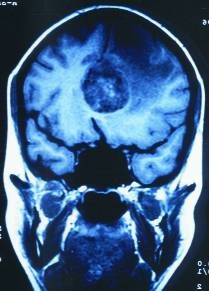

Für uns stellt diese zufällig gemachte Kernspintomographie einen wissenschaftlichen „Glücksfall“ dar, weil uns Kernspinaufnahmen, die nach solch langer Konfliktdauer in der gerade beginnenden Heilungsphase zufällig genau im „richtigen Moment“ gemacht worden sind, ein außergewöhnlich gut sichtbares Phänomen demonstrieren (mit Kontrast links, ohne rechts):

Wir sehen im Inneren des gerade in Lösung gehenden großen Hamerschen Herd (HH) noch die alten Schießscheibenringe, die nur noch kurz so gut zu sehen sind, weil sie dann im Oedem verschwimmen.

Normalerweise können wir mit dem Kernspin-Tomogramm Schießscheibenringe des HH erst nach 2 bis 3 Jahren Konfliktdauer erkennen. Und dann färben sie sich ja auch nicht mit Kontrastmittel an.

Hier aber hat der Radiologe zufällig den richtigen Tag erwischt und zufällig auch die richtige Aufnahmetechnik, mit Kontrastmittel.

Die Schießscheibenringe tauchen noch einmal wieder auf und färben sich in der pcl-Phase weiß an, um dann meist im Oedem zu verschwimmen.

Auf der rechten Aufnahme ohne Kontrastmittel ist praktisch kein Ring zu sehen.